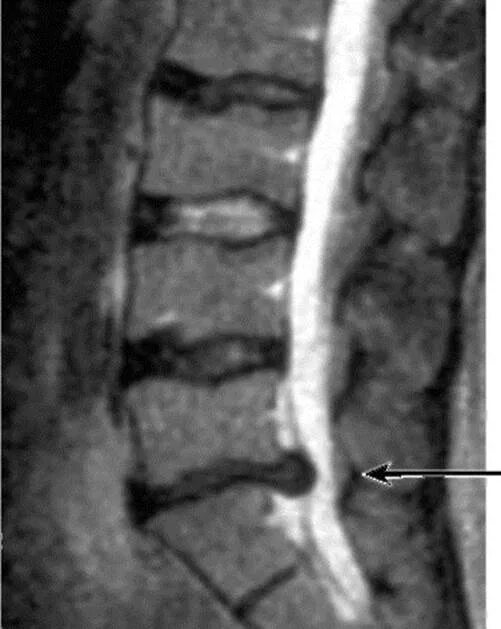

Дегенерация межпозвонкового диска по pfirrmann